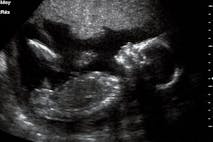

The development of the child in utero is the ultimate reality show